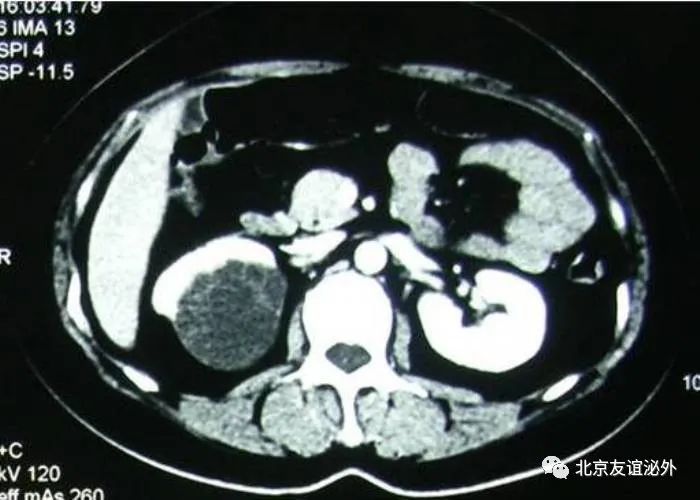

图5. Bosniak IIF级恶性囊肿(高密度囊肿,肾乳头状细胞癌)